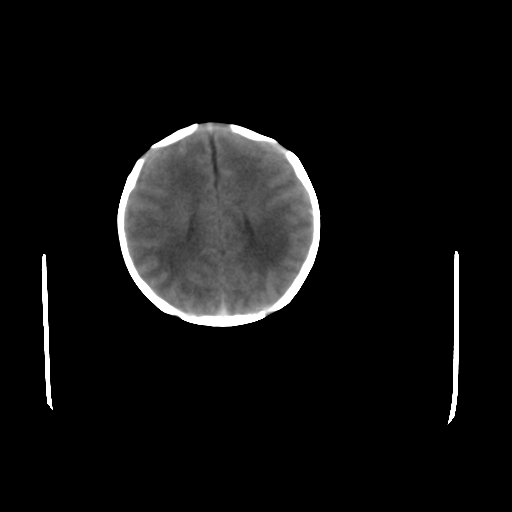

疑问:患儿脑白质密度比较低,基底节区密度比较高,类似于“双圈征”脑沟密度也偏高。该婴儿可有别的异常吗?反射正常吗?评分能达到5分吗?如果正常,就随诊观察吧。不正常要考虑到缺血缺氧性脑病。

鉴别:骨膜下血肿,一般为产伤,应用产钳之类的吧